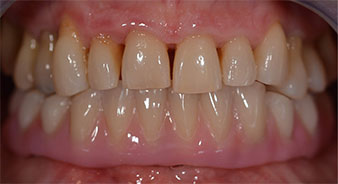

Following an explanation of the various treatment options open to her, the patient decided on extraction of the residual dentition in the mandible, an immediate implantation and treatment with the Fast & Fixed method (bredent medical), whereby the provisional fixed denture is screwed onto four implants on the same day as the surgery. The goal was to operate on the patient on the Friday so that she could assist in the oral examinations on the following Monday.

A three-dimensional cone beam computed tomography scan (CBCT, Planmeca) was performed to aid planning and minimize risks. This revealed that the quality and quantity of the available bone were sufficient for the surgery and immediate restoration using the Fast & Fixed method. Following the protocol for this concept, the implants are inserted at 35, 32, 42 and 45. Angling the distal implants by up to 45° shifts the emergence profile to posterior and generates a larger support polygon (Fig. 3).